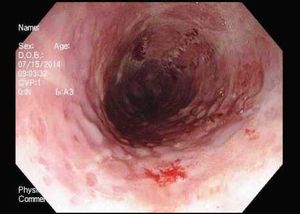

A 28-year-old man reports pain on swallowing of a week's duration. He is otherwise in good health. Upper endoscopy and tissue biopsy reveal the cause. What do you see?

The most frequently encountered cause of infection of the esophagus is Candida. Among viral causes HSV is the most common, followed by CMV.